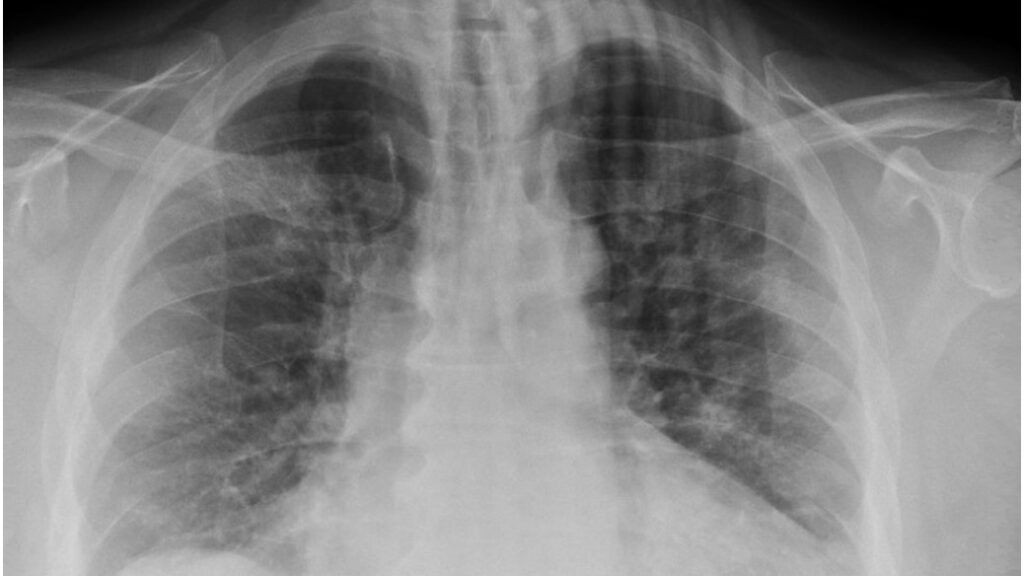

Hal tersebut disebabkan karena varian omicron mempengaruhi paru-paru secara berbeda.

Menurut para ilmuwan yang melakukan penelitian, yang melibatkan percobaan pada tikus dan hamster, omicron menyebabkan dampak yang tidak terlalu parah pada saluran pernapasan bagian atas dan bawah.

Mereka menemukan bahwa strain menghasilkan “beban virus yang lebih rendah” di hidung, tenggorokan, dan paru-paru, yang mengarah ke viral load dan replikasi yang lebih ringan dan, pada akhirnya, lebih sedikit kerusakan pada area yang disebutkan.

Para peneliti menunjukkan bahwa mereka melihat infeksi yang dilemahkan atau melemah di paru-paru hewan pengerat.

Tikus dengan varian baru SARS-CoV-2 hanya mengalami penurunan berat badan yang terbatas dan beban virus yang lebih rendah di saluran pernapasan mereka.

Dokter-ilmuwan dan ahli imunologi mengatakan bahwa meskipun omicron bereplikasi lebih cepat di bronkus, ada bukti bahwa strain bereplikasi lebih lambat di paru-paru.

Tim di balik penelitian ini mengatakan bahwa omicron berkembang biak sepuluh kali lebih lambat di jaringan paru-paru dan 70 kali lebih cepat di saluran udara dibanding versi asli SARS-CoV-2.

Karena omicron bereplikasi pada tingkat yang lebih lambat di paru-paru, ini dapat menjelaskan tingkat keparahan penyakit yang lebih rendah.